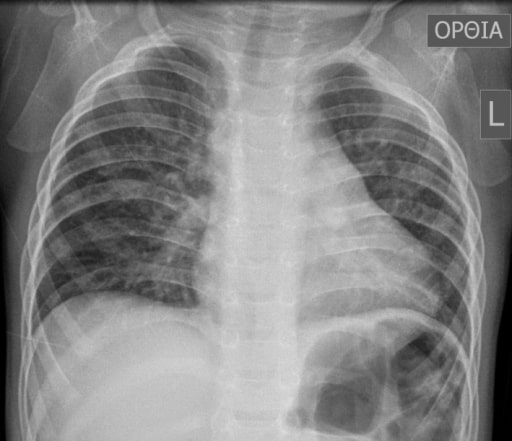

Boot-shaped heart: chest X-ray of a 16-month-old boy with tetralogy of Fallot

Image: “Typical preoperative chest X‐ray of a 16‐month‐old boy with tetralogy of Fallot” by Andrew C. Chatzis et al. License: CC BY 4.0